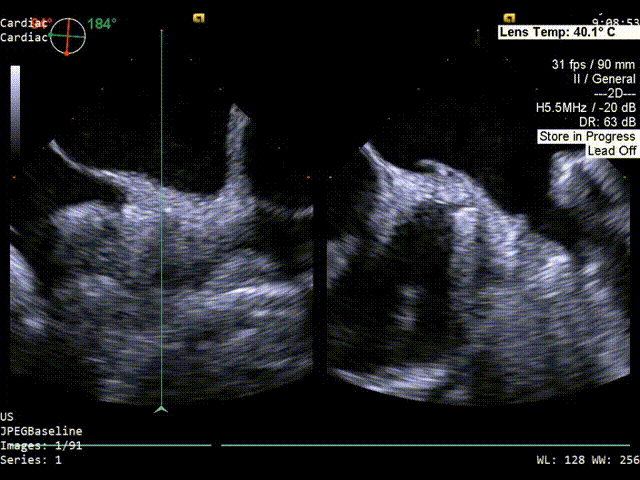

color超声影像

1、PFO结构:静息状态下房水平见左向右分流。继发隔厚约5mm;原发隔厚约0.84mm;未探及下腔静脉残瓣及希阿里氏网。

该患者卵圆孔呈长隧道、巨大且形态不规则,压缩缝合器操作空间;同时,继发隔迂曲,缝合器捕捉和固定组织挑战大,常规缝合难以保证最佳闭合效果。